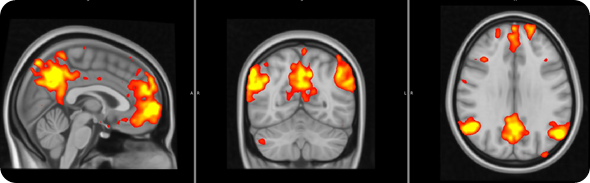

In order to address this question, we used a brain imaging technique called ‘functional Magnetic Resonance Imaging’, which allows us to examine how brain activity changes in association with certain states or tasks.

In this study brain activity was investigated when the participants received painful stimuli, as well as when they received visual cues informing the subjects of impending pain onset (pain anticipation) and pain offset (relief anticipation).

We saw that the healthy subjects showed large brain responses, in many regions, when they were anticipating pain or relief. Some of these changes are likely to be due to the detection of ‘salient’ event. In other words, some of these responses may be non pain-specific and may simply reflect the fact that the subjects were detecting an ‘interesting event’.

However, other responses would seem to be even more interesting, and possibly pain specific: for instance the healthy volunteers activated a region called the ‘periaqueductal gray region’, which we know exerts a modulatory effect on the pain signals coming to the periphery (this is a region that if stimulated electrically can alleviate pain).

The healthy volunteers also showed that a region involved in the processing of ‘reward’/’punishment’, the so called ventral tegmental area (VTA), was activated during pain anticipation, and deactivated during relief anticipation.

FM patients exhibited reduced brain responses in response to visual cues for both pain anticipation as well as relief anticipation.

This reduced responsiveness was very widespread, and included the periaqueductal gray and the VTA.